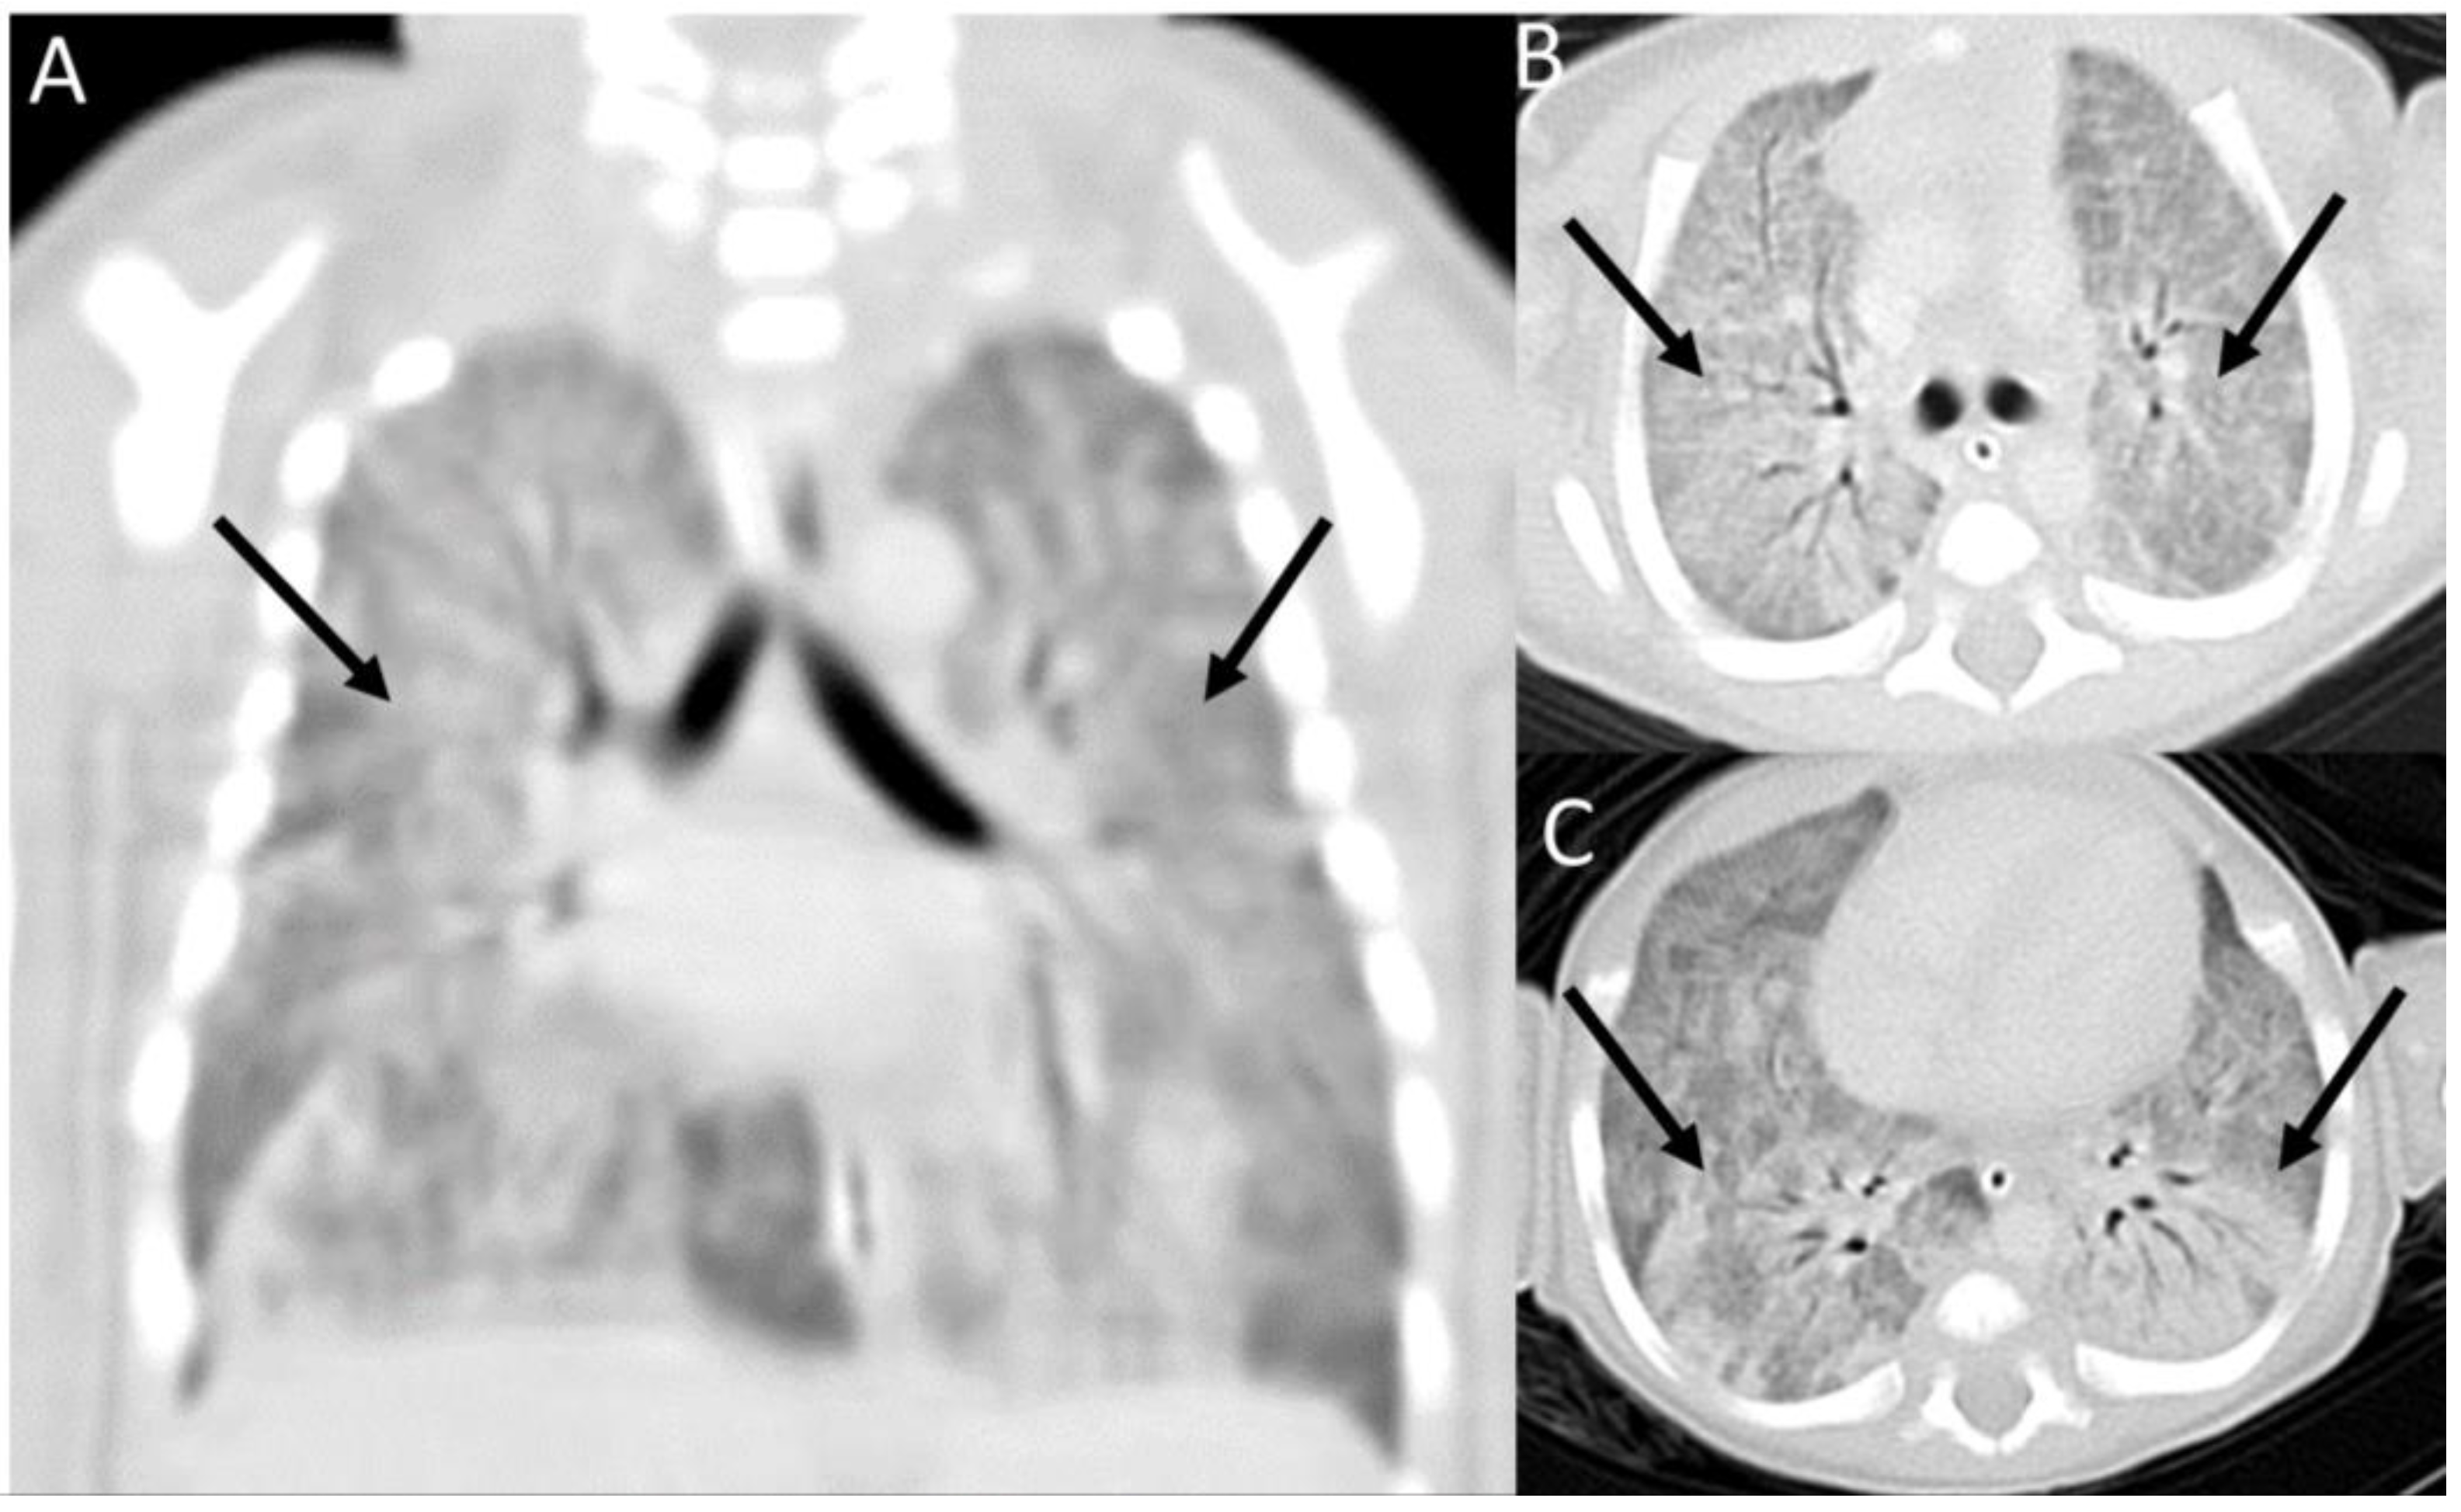

2. Case Presentation